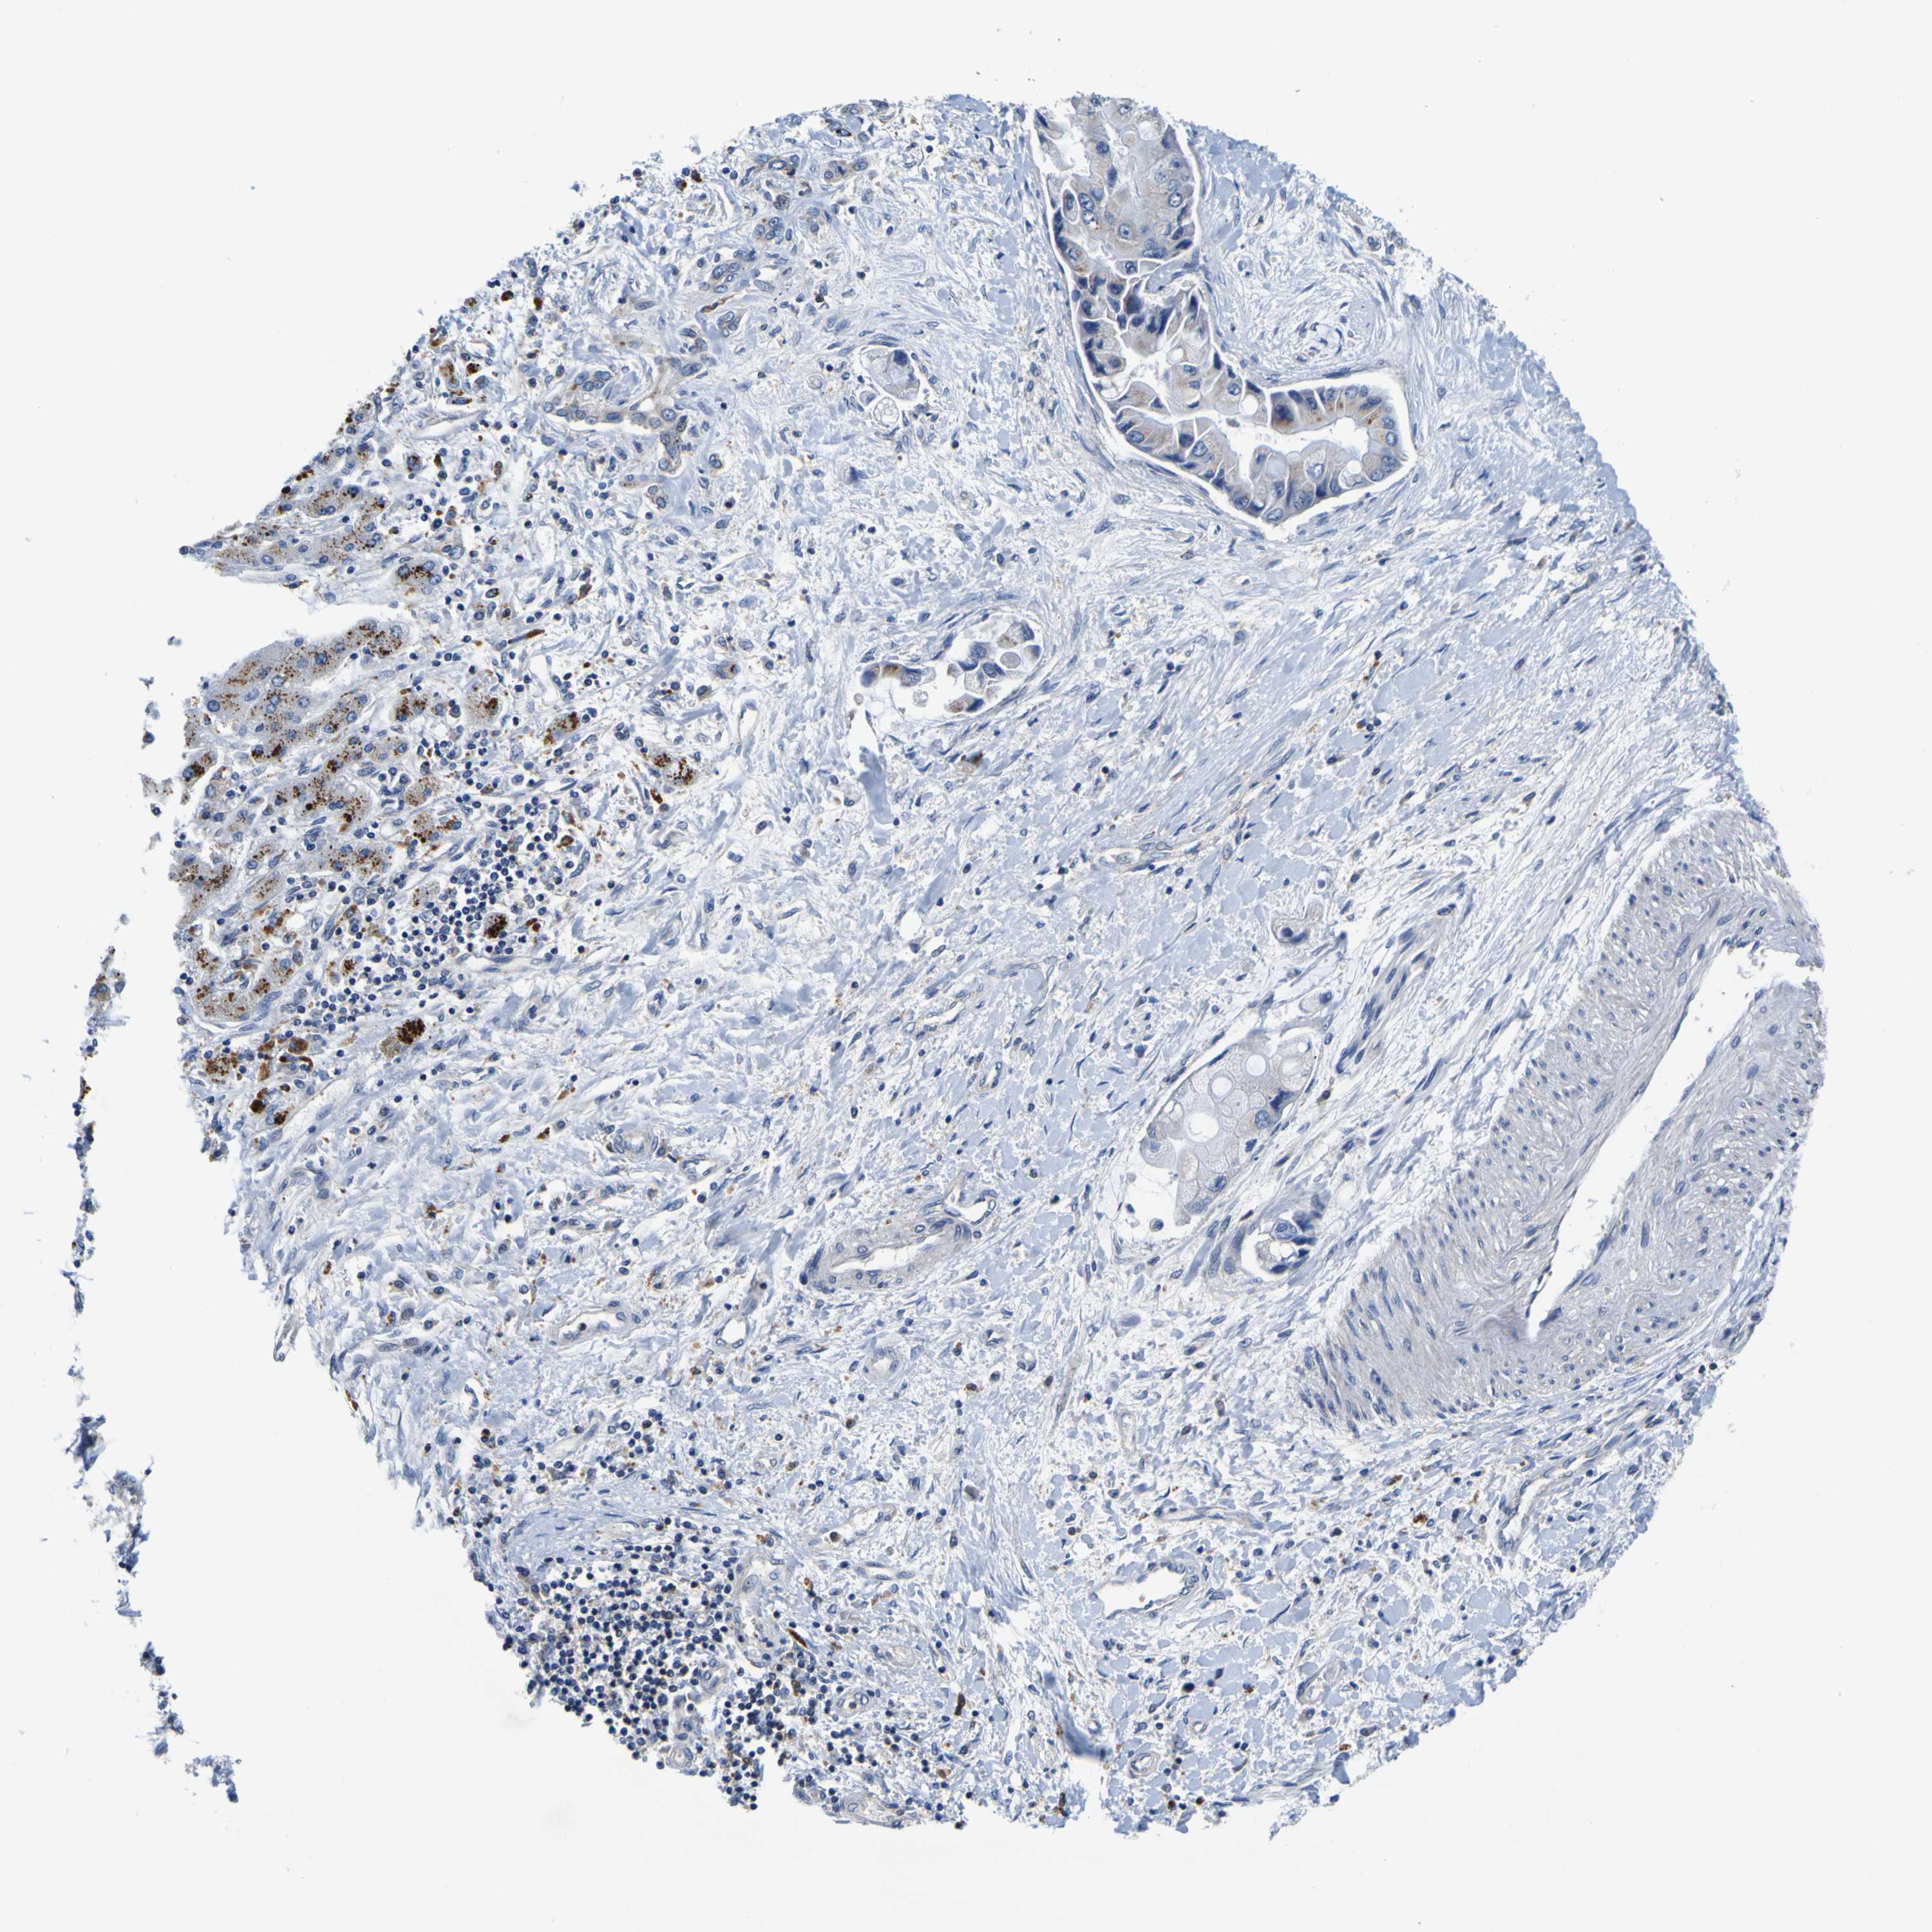

LIVER CANCER - Protein expressioni

A mouse-over function shows sample information and annotation data. Click on an image to view it in a full screen mode. Samples can be filtered based on level of antibody staining by selecting one or several of the following categories: high, medium, low and not detected. The assay and annotation is described here.

Note that samples used for immunohistochemistry by the Human Protein Atlas do not correspond to samples in the TCGA dataset.

Antibody stainingi

Antibody staining in the annotated cell types in the current human tissue is reported as not detected, low, medium, or high, based on conventional immunohistochemistry profiling in selected tissues. This score is based on the combination of the staining intensity and fraction of stained cells.

Each image is clickable and will lead to virtual microscopy that enables deeper exploration of all samples and also displays staining intensity scores, fraction scores and subcellular localization as well as patient and tissue information for each sample.

Antibody HPA012128

Antibody HPA012297

Staining

High

Medium

Low

Not detected

Intensity

Strong

Moderate

Weak

Negative

Quantity

>75%

75%-25%

<25%

None

Location

Nuclear

Cytoplasmic/membranous

Cytoplasmic/membranous,nuclear

Cholangiocarcinoma

Carcinoma, Hepatocellular, NOS